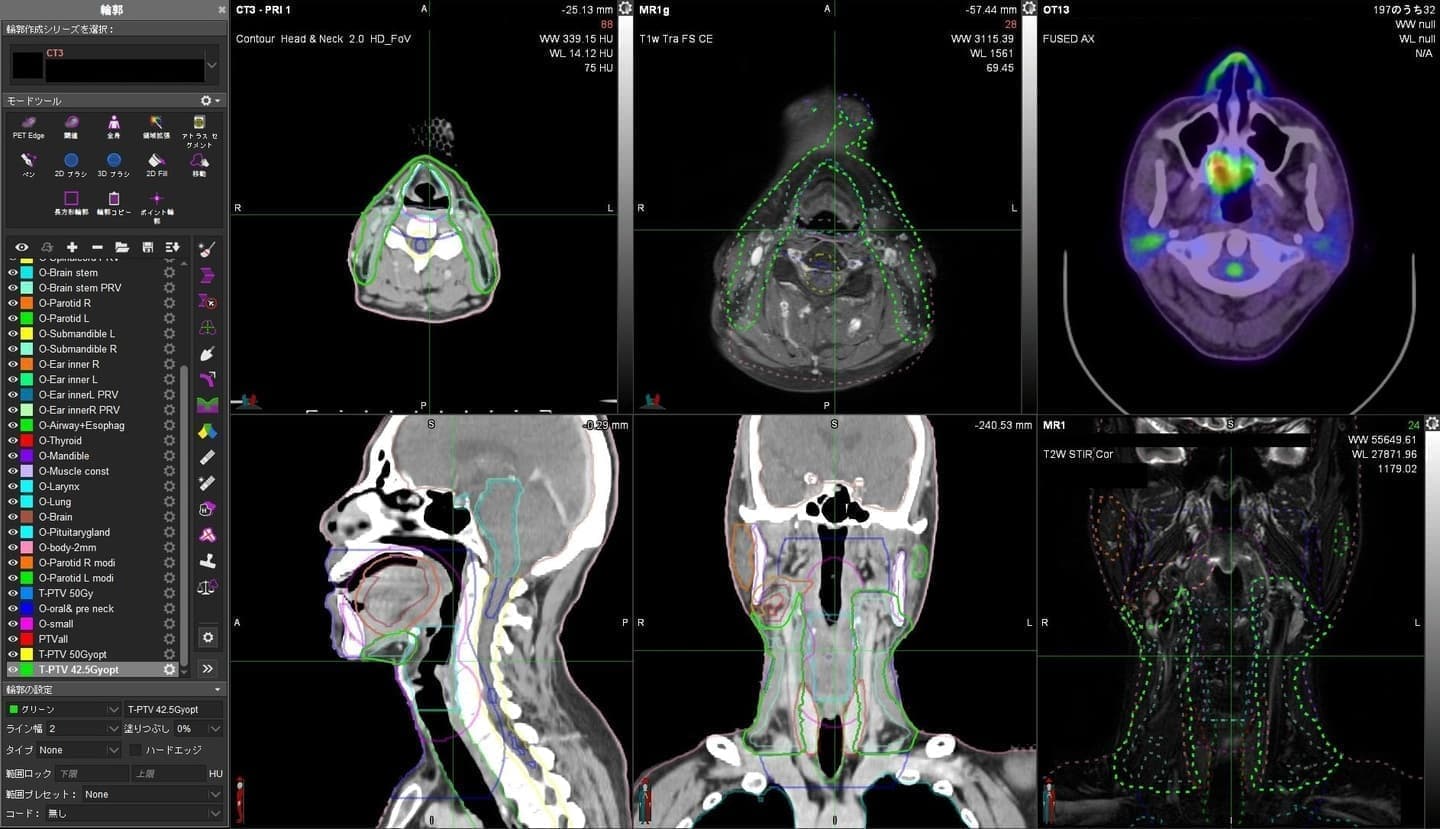

当院では、放射線治療計画の精度と効率を飛躍的に向上させるため、SIEMENS社製のAI-Rad Companion Organs RT (AIRC Organs RT) を導入しています。

AI-Rad Companion Organs RTとは

これまで、放射線治療計画には、放射線腫瘍医がCT画像を見ながら一つひとつの臓器の輪郭を手作業で描出するという、時間と労力のかかる作業が伴っていました。しかし、AIRC Organs RTは、CT画像から臓器の輪郭を人工知能(AI)が自動的に描出する画期的な技術です。

現在、160以上の臓器に対応しており、CT撮影後の画像データをAIRC Organs RTへ送信するだけで、約5~10分という短時間で自動的に臓器の輪郭描出が完了します。

AIが作成した輪郭は、放射線腫瘍医が最終的に確認し、必要に応じて修正を加えます。

この先進技術を活用することで、これまで以上に迅速かつ精度の高い放射線治療を患者様にご提供できるよう努めてまいります。